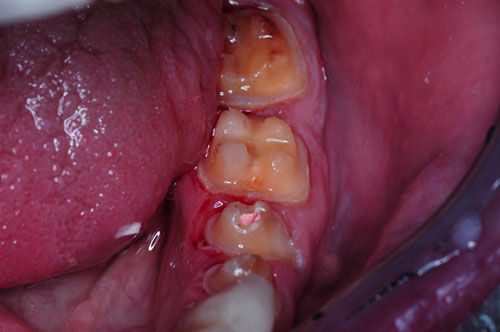

Comenzamos desmontando los sectores posteriores, lo que constituye un camino a la inversa de como se debe montar una Rehabilitación Oral.

Comenzamos por el sector superior derecho, instalando nuestros provisorios del sector y ganando la mitad del espacio creado en el articulador.

(Nótense los mini desgarros gingivales producto de un tallado infragingival por alisado radicular, con la consecuente retracción de encía a fín de que el borde cavo superficial de la preparación racional . termine siendo supragingival para facilitar el cepillado)